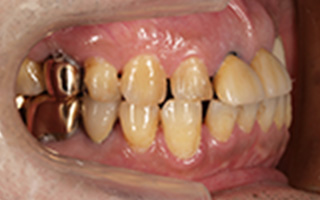

Before

After

| 68歳 男性 | 紹介 |

|---|---|

| 主訴 | れ歯が合わない 食べにくい 人生を豊かにしたい |

| 処置内容 |

上顎4本で12歯(オールオン4)、下顎4本5歯 上下抜歯即時埋入、即時荷重(手術当日にインプラントの上に仮歯装着) |

| 治療費用 | 上顎: 約220万(税込) 下顎: 約180万円(税込) |

| 治療期間 | 上顎: 9ヶ月 下顎: 6ヶ月 |

| リスク |

術後の腫れ、痛み(ピークは3日後、1週間で軽減) 上部構造物、仮歯の破折、人工歯根脱落リスクがあります |